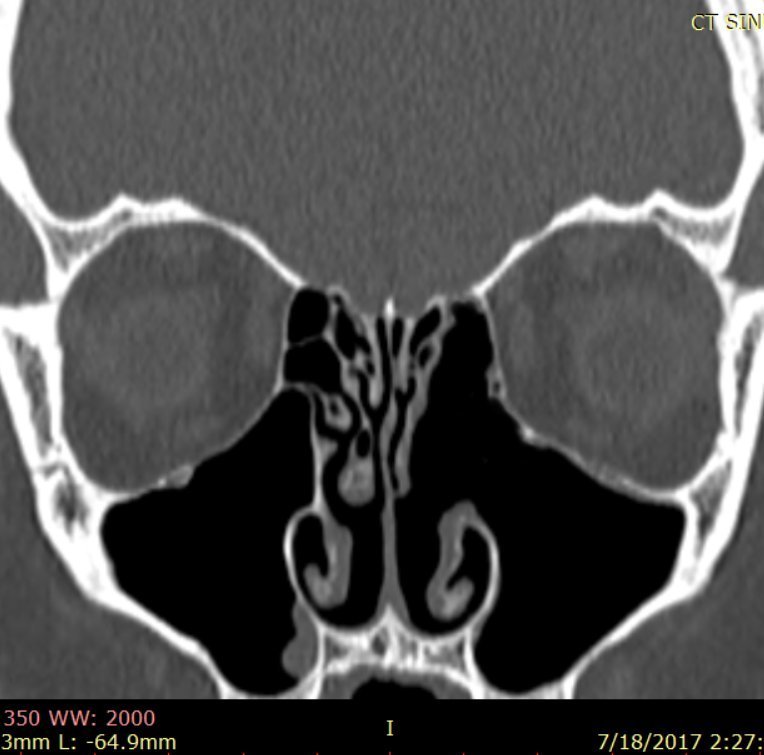

Pacienta efectuase încă din anul 2015 un examen RMN craniocerebral pentru explorarea lojei hipofizare în contextul SIADH, în care se putea vizualiza cu uşurinţă patologia tumorală rinosinusală, însă examenul ORL efectuat la acea dată a stabilit diagnosticul de polipoză nazală unilateral – fig. 1

Fig. 1: examen RMN craniocerebral cu substanță de contrast efectuat în anul 2015